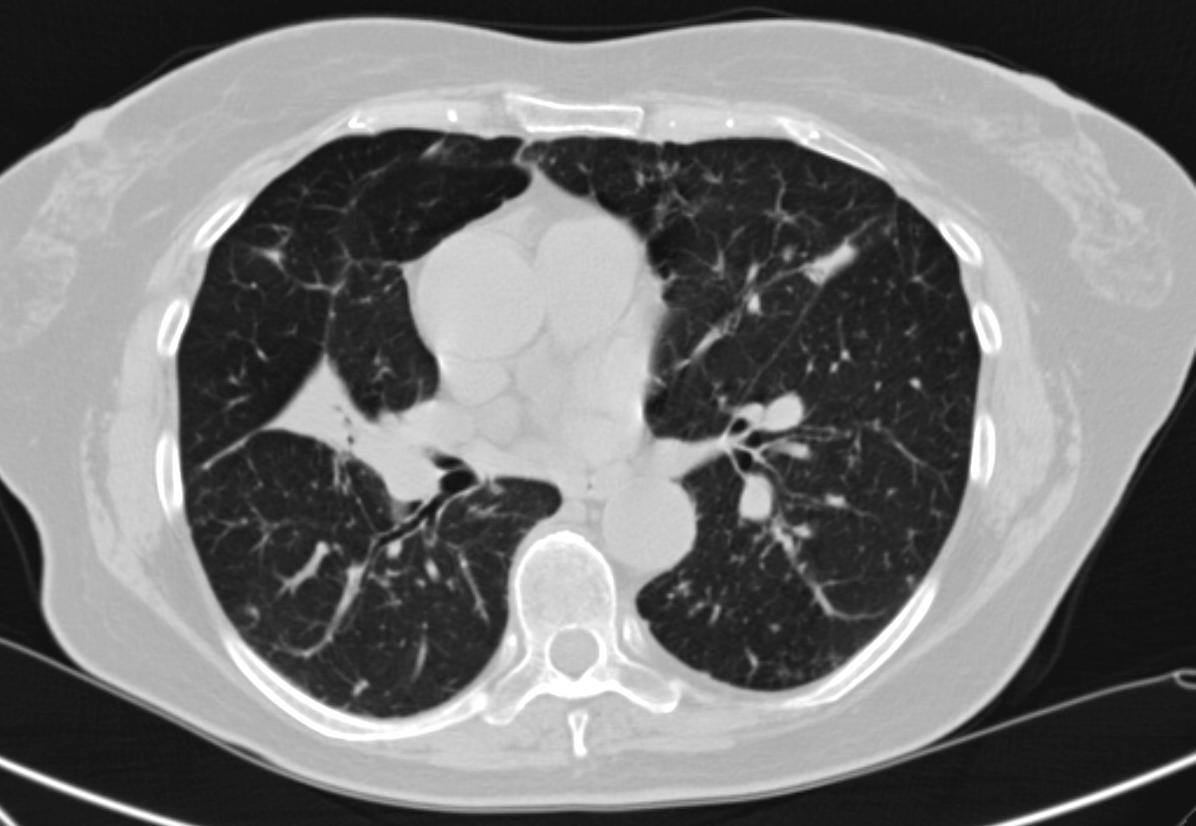

3b: Multiple lung metastasis, CT lung window (axial, coronal reformat)

Image

3c, coronal reformat

70 year old man, colon tumor.

Radiograph: Bilateral extensive, confluating patchy-nodular shadowing with diffuse reticular pattern. The diaphragm contour is partially blurry bilaterally: lymphangiosis carcinomatosa.

CT: Numerous 1-6 cm round and irregular, lobulated-spiculated contrast enhancing lesions in both lungs, everywhere sporadically.